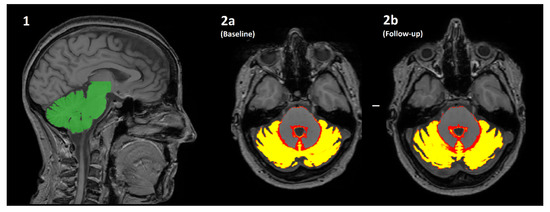

Figure 1.

An overview of how the volume of cerebellar grey matter is estimated using the SUIT pipeline. (1) The cerebellum is automatically identified (green) and segmented from the original T1-weighted image. (2a/2b) The cerebellum is then further segmented into a “tissue probability map”, where the value of each pixel is transformed into the % probability that it is brain grey matter. The mean of all pixels with a non-zero value is multiplied by the volume of all such pixels (i.e., the mean*volume of red/yellow regions) for both the baseline (2a) and follow-up (2b) scans. The difference in values is the estimated change in volume over time, which is further normalised by the actual length of time between scanning sessions to produce percentage yearly brain volume change (pYBVC).